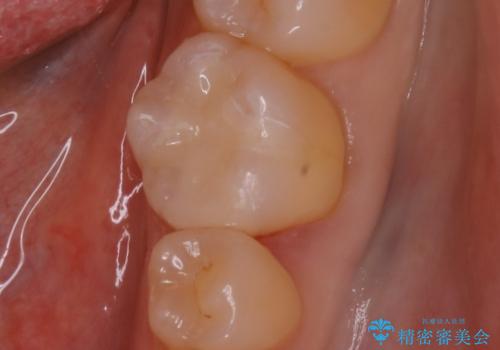

穴があいたクラウンのやり直しは根管治療から

- 穴のあいてしまった被せものは除去し仮歯へ

→根管治療をやり直し、土台を立て直す

→新たにクラウンを製作する

根管治療からのやり直しは時間と労力がかかりますが、基礎の部分をしっかりと仕上げることで、安心して長く使っていただく事ができると考えています。

被せものの種類:Bellezza